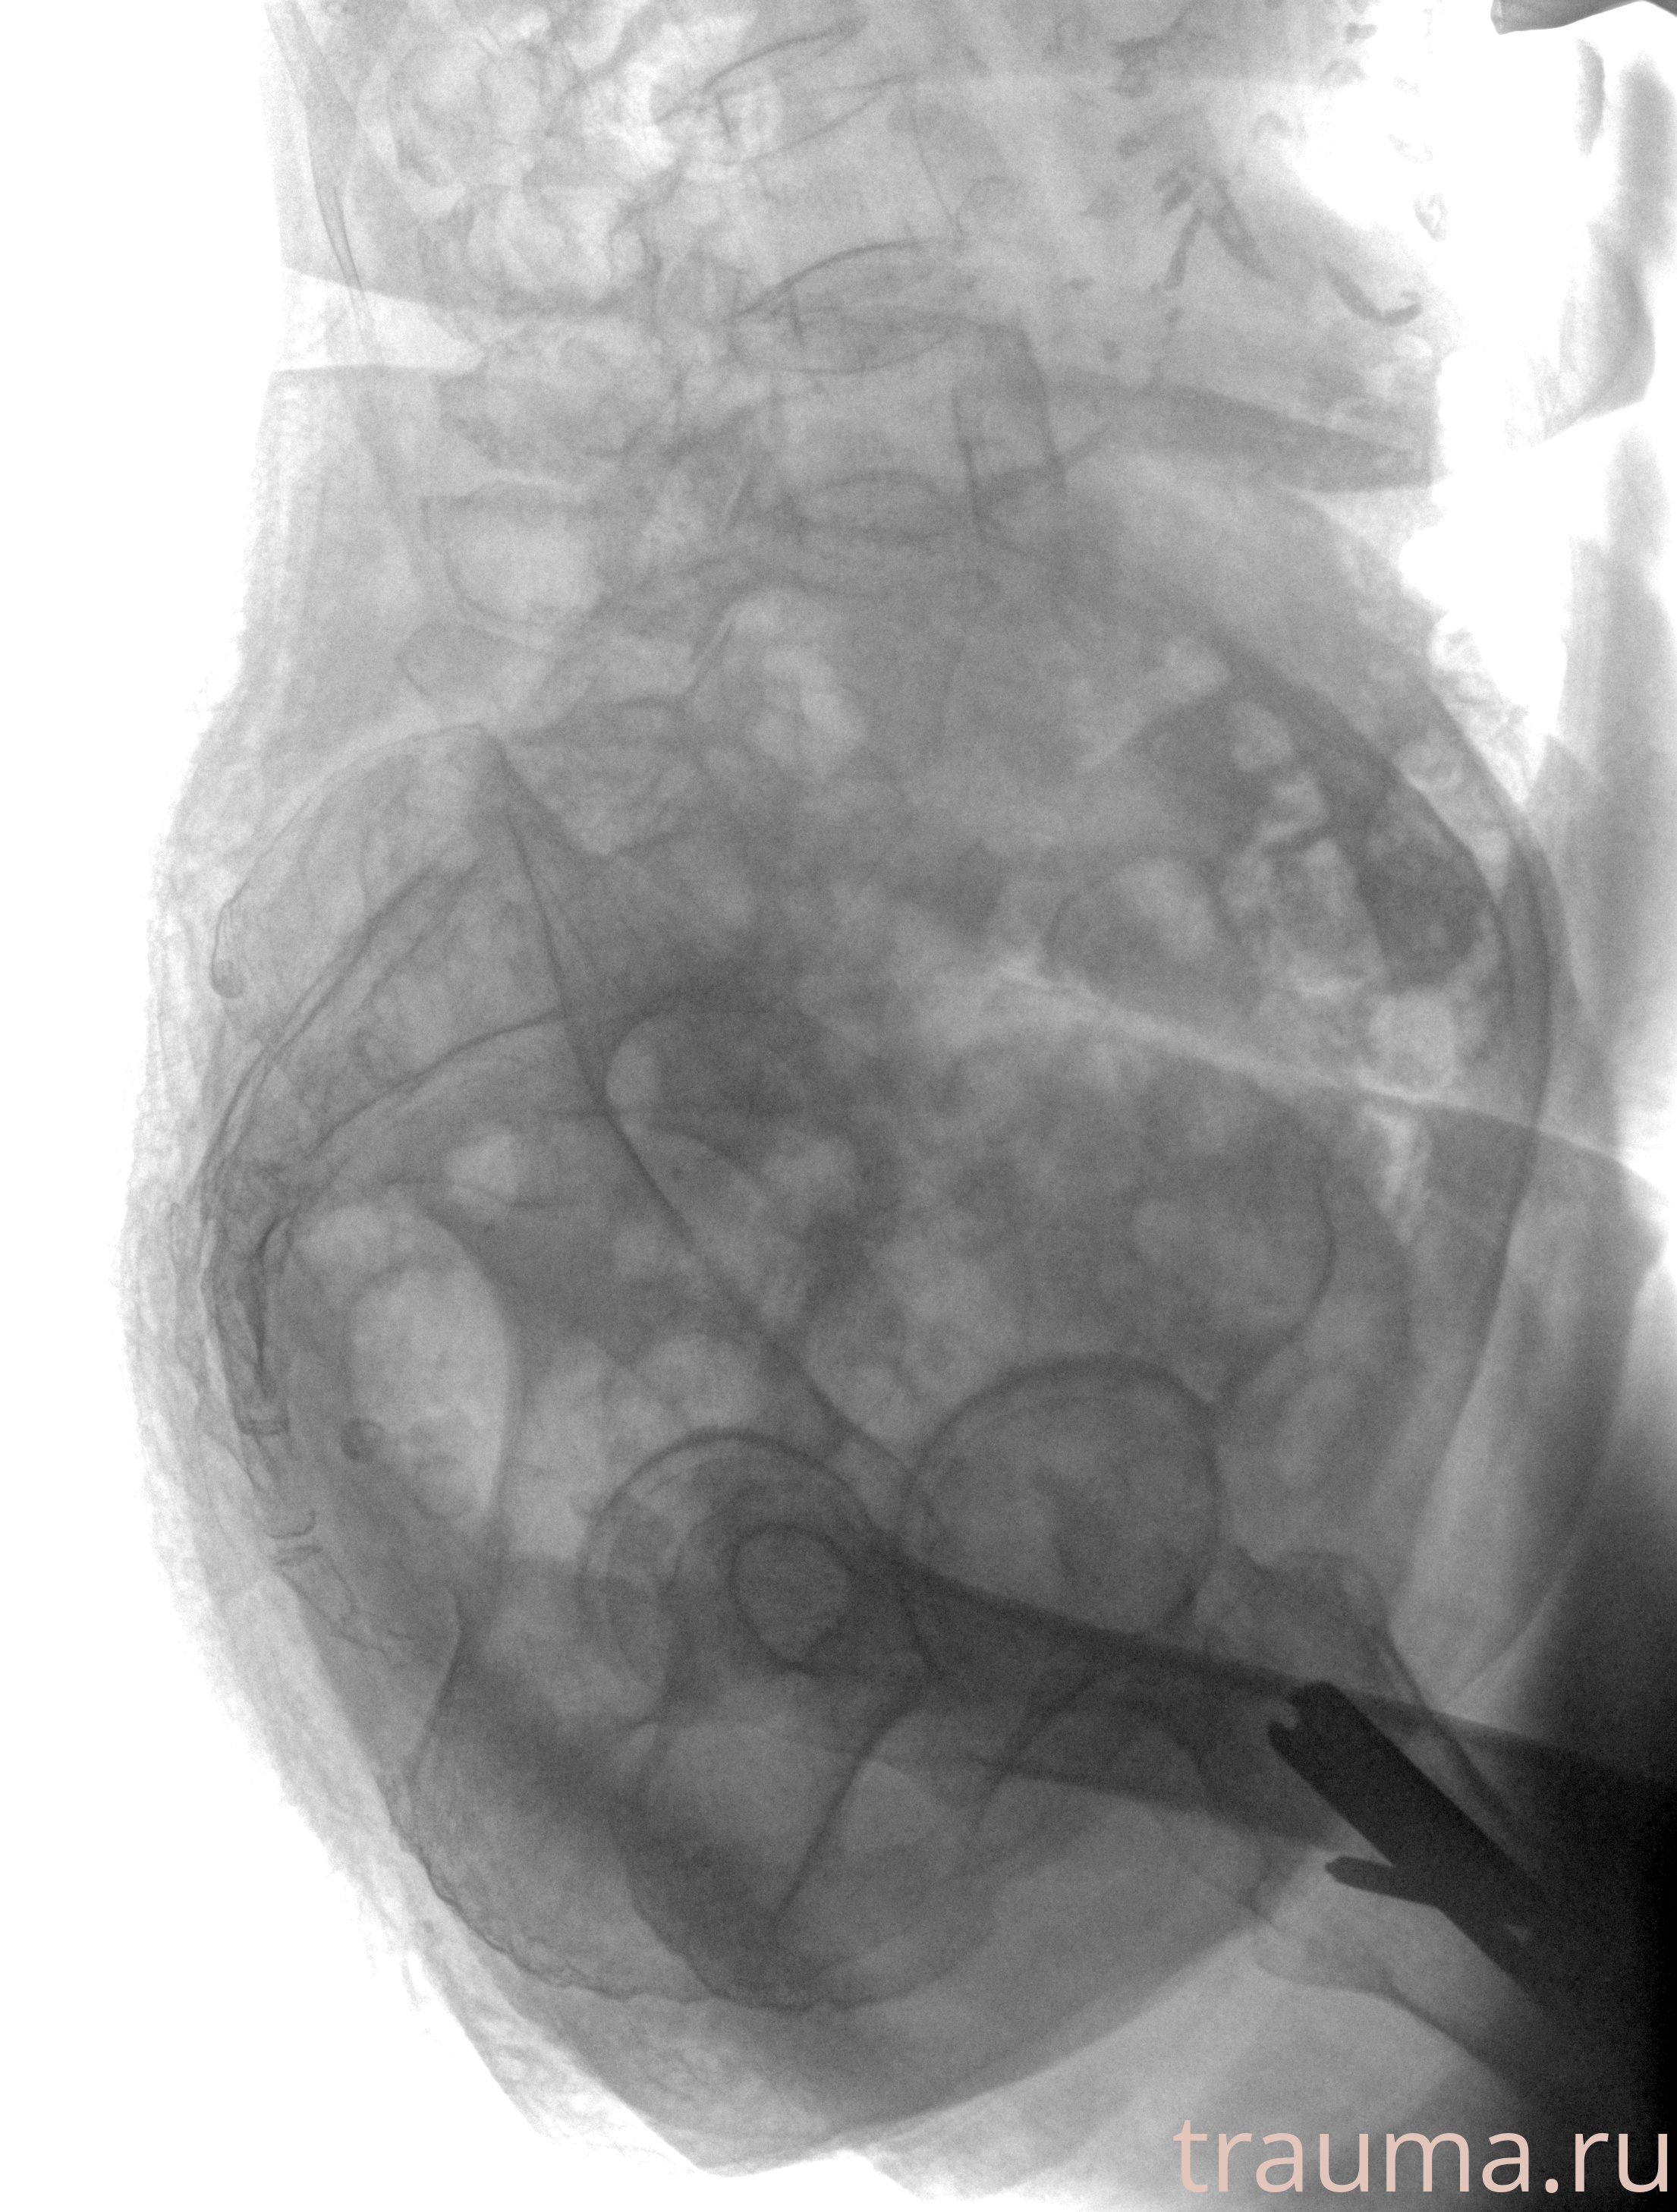

Рентген на дому: по вашему адресу приезжает врач-рентгенолог, травматолог-ортопед с мобильным рентгеновским аппаратом, проводит диагностику травмы или заболевания, делает необходимые рентгенограммы, дает рекомендации по дальнейшему лечению. Получить качественные снимки в домашних условиях возможно благодаря уникальной методике, разработанной МосРентген Центром для института  Склифосовского